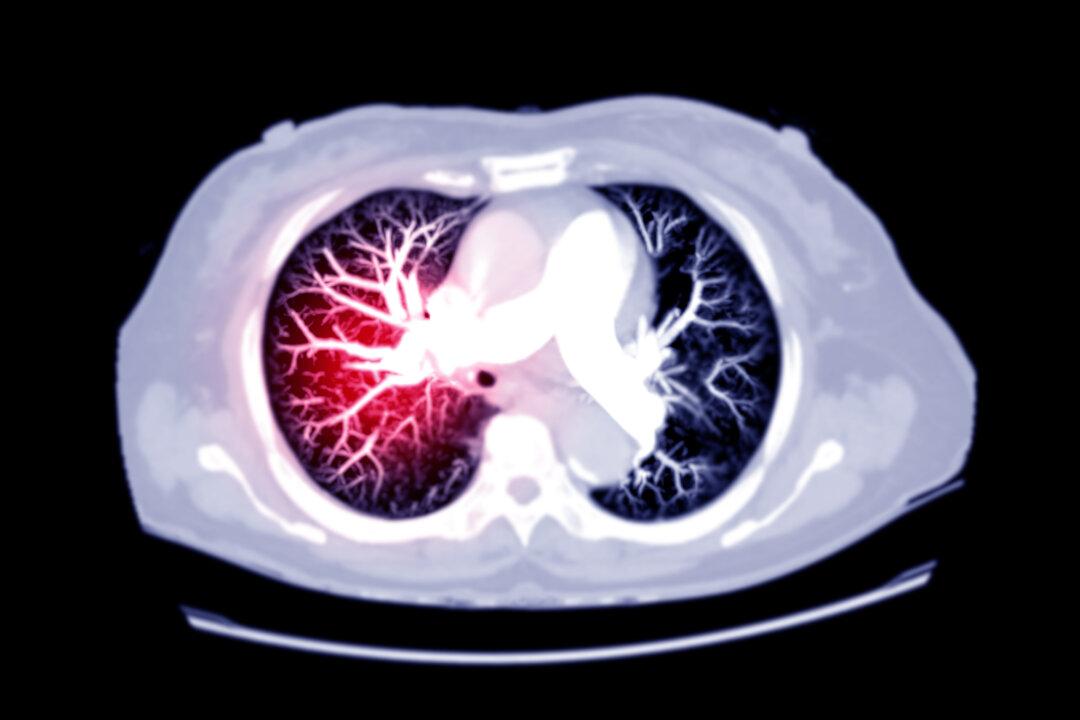

Baker nervously went on to say that masks were still necessary and that we all had to get the shot for it really to work on a population level. At that time, papers were pouring into the medical literature that SARS-CoV-2 viral infection was causing blood clots and the causative agent was the Spike protein.[ii] While the consent form likely did not mention blood clots, Baker could have covered his bases by saying the vaccine is new, that all of its side effects are not known, and that we do not have assurances that it protects against COVID-19 for more than two months.